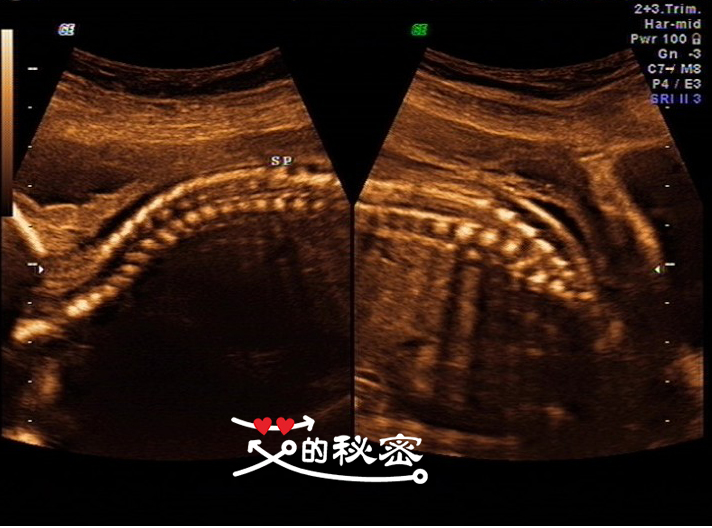

10、胎儿脊柱:颈、胸、腰、骶尾段排列形态未见明显异常,SP表示脊柱的意思。

6、脊柱畸形的筛查是要重点视察脊柱有无隆起,光带有无中断,排列有无紊乱,骶尾部有无肿块等。